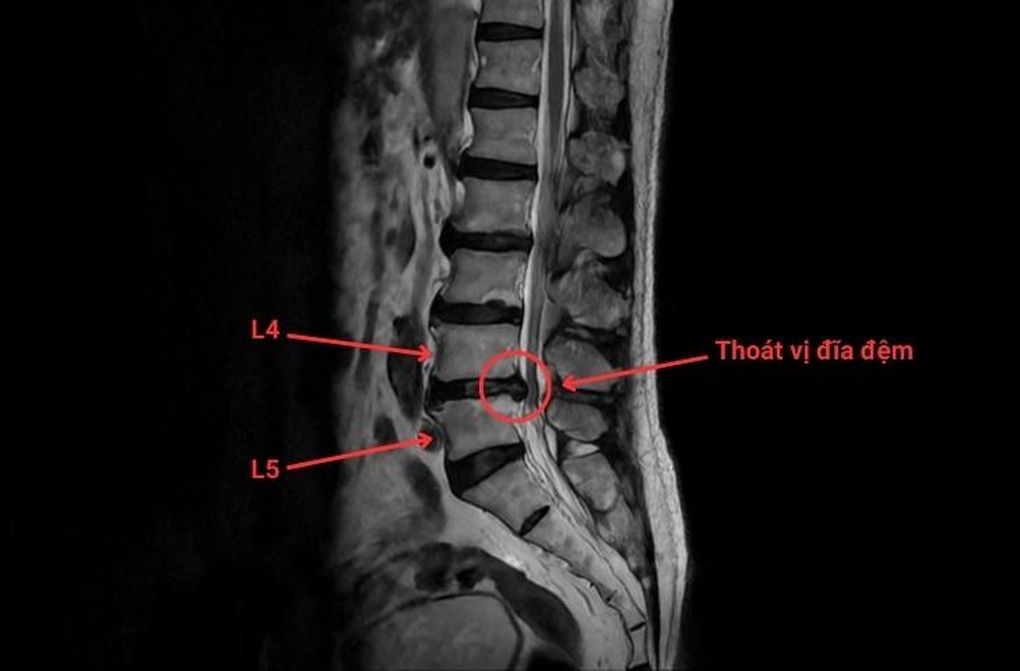

Phim chụp thoát vị đĩa đệm cột sống thắt lưng L4/L5 (Ảnh: BVCC).

Hay trường hợp của bệnh nhân Q (63 tuổi) bị đau lưng mạn tính do thoát vị đĩa đệm chèn ép rễ thần kinh tại vị trí L4/L5 khiến bệnh nhân phải ngủ trong tư thế quỳ. Gần đây bệnh nhân gặp tình trạng tê bì, yếu chi, đi lại khó khăn. Khi các phương pháp điều trị nội khoa không đáp ứng, bệnh nhân được chỉ định thăm khám và can thiệp chuyên sâu.